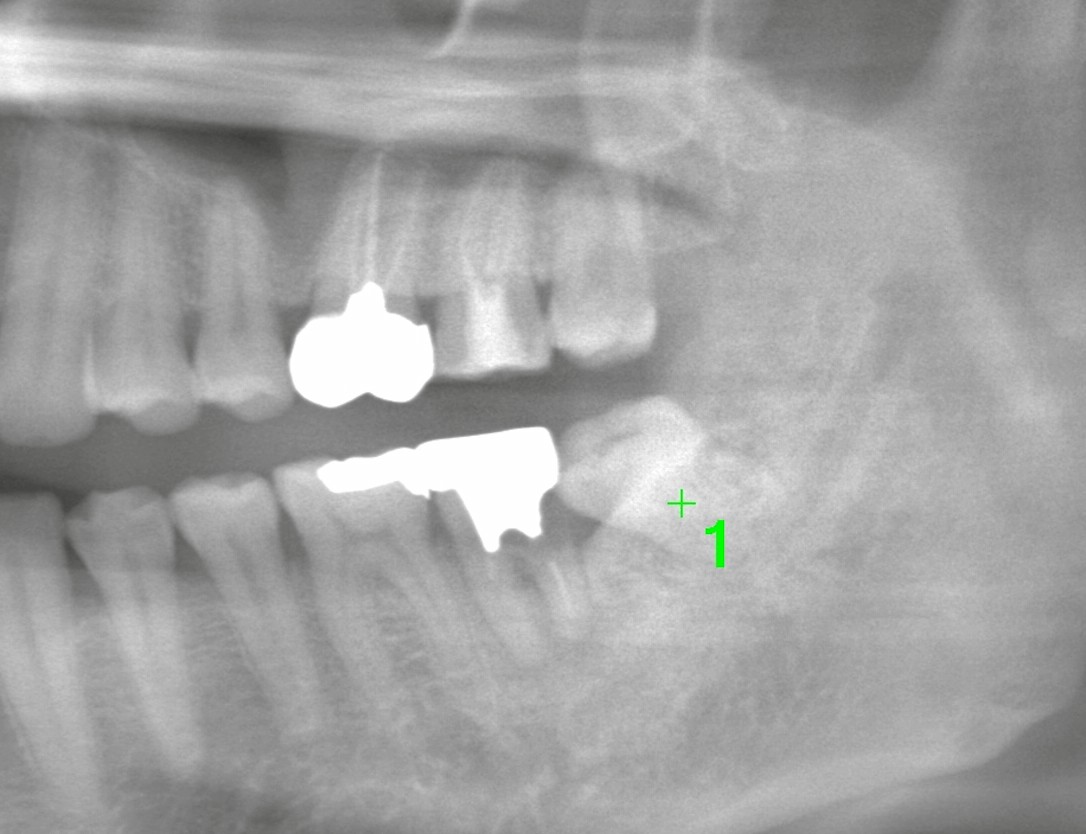

この患者さまの親知らずは二根性で太く、しかも手前の歯が弱っているという難しい特徴がありました。

一時は「移植(歯牙移植)」も検討しましたが、CT精査の結果——

* 抜歯窩とサイズ不一致

* 親知らずの二根が湾曲し、分割抜歯が必要な可能性

* 術後安定性が十分に得られない

これらを踏まえ、移植は適応外と判断。